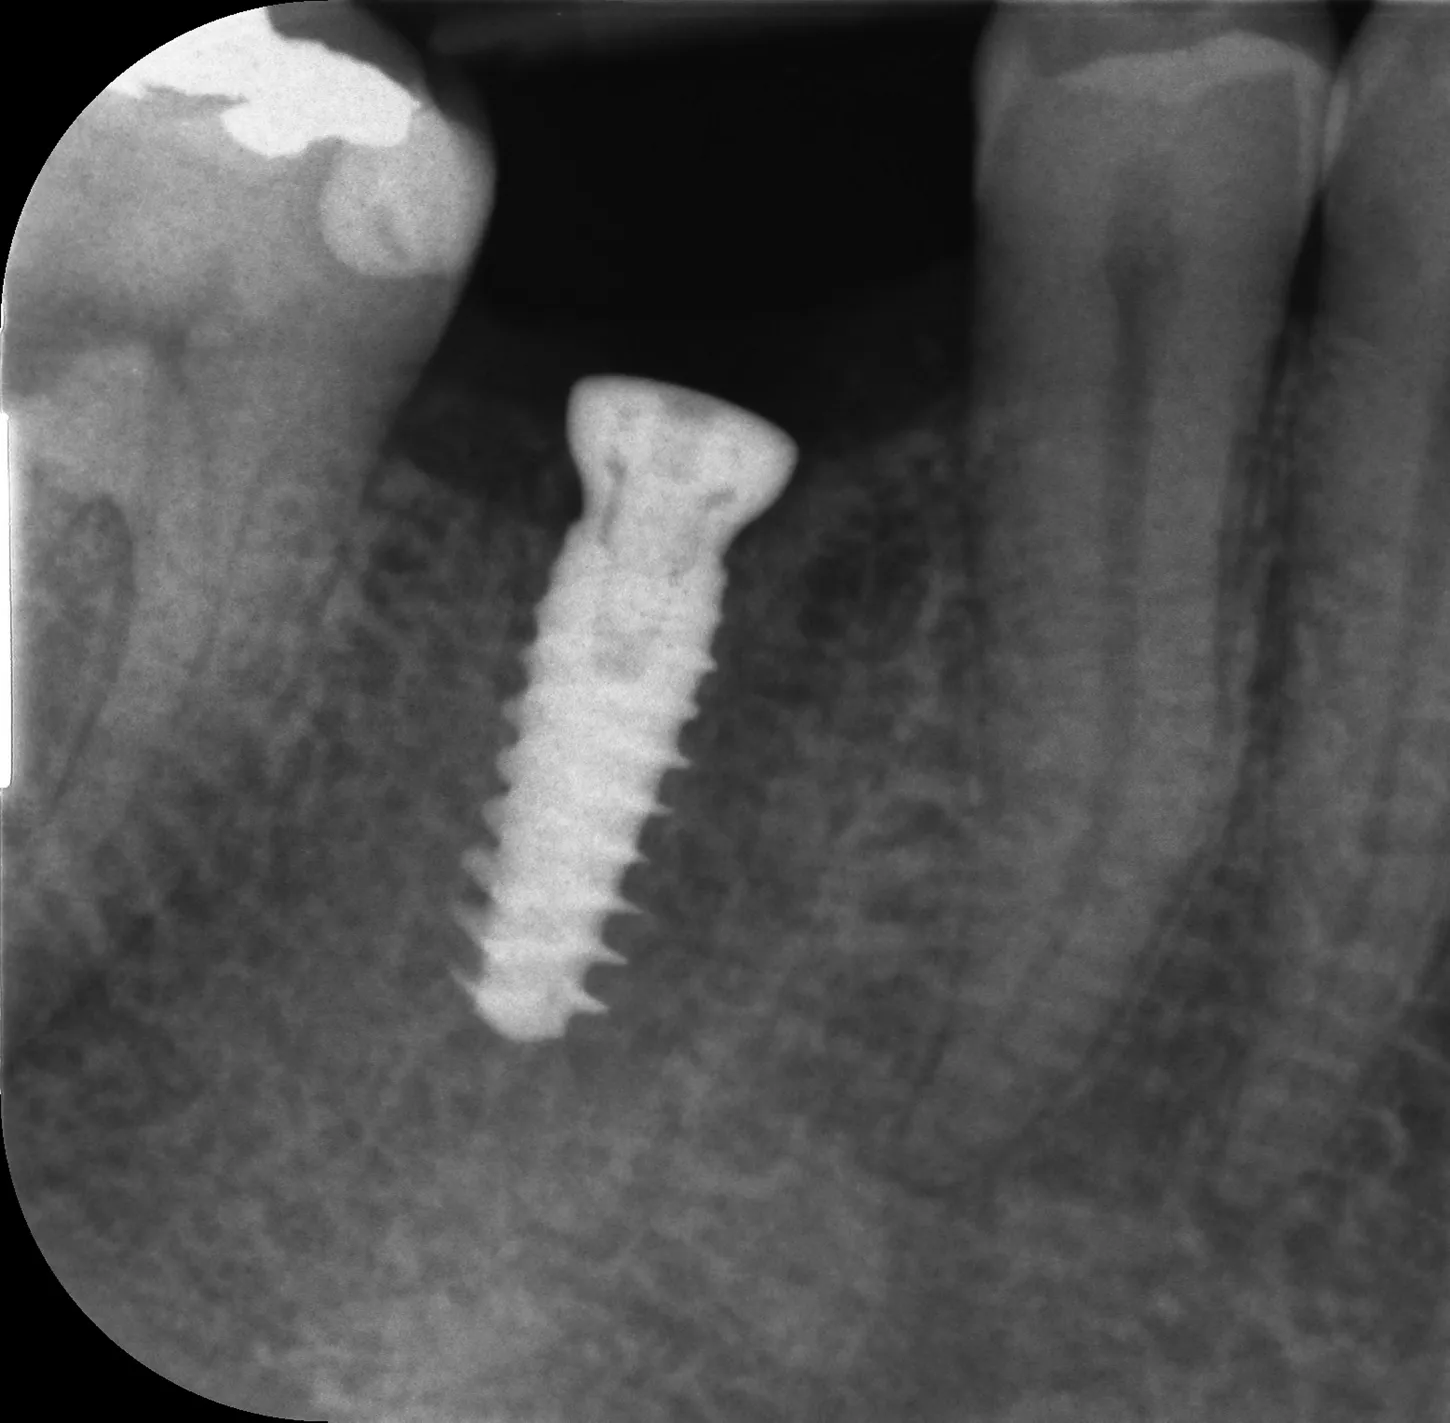

12. Après une période de cicatrisation de 12 semaines (qui s'est déroulée sans incident), le patient est venu pour les empreintes finales. Une radiographie a été prise et un remodelage osseux a été observé.